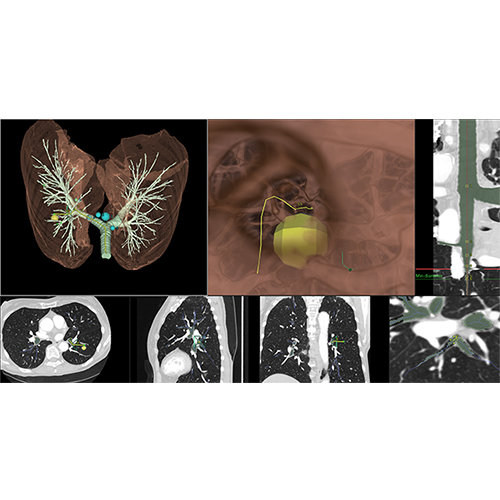

View X-Ray CT & MRI Scans Fast and Easily

Designed for surgeons, Pro Surgical 3D makes it easy to view patient scans quickly. Pro Surgical 3D facilitates the optimal 3D treatment and assessment workflows based on X-ray CT and MRI scans – and best of all, it’s FREE!

Traditional multi-planar slicing

High-quality and fast 3D reconstruction and 3D rendering

Performs 3D reconstruction and volume rendering.

Multi-planar slicing.